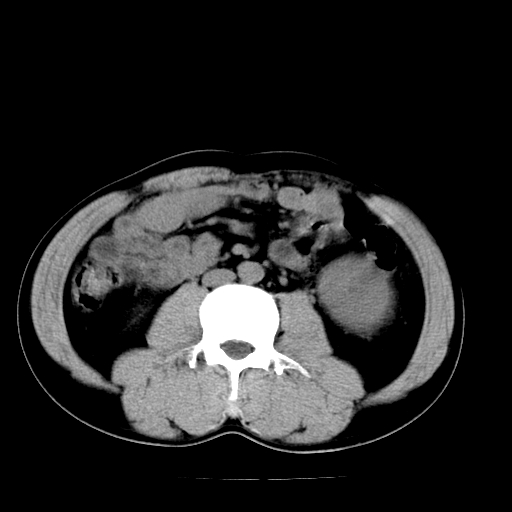

以下是引用天南地北在2007-4-30 13:36:00的发言:[br]支持慢性胰腺炎伴有假性囊肿

以下是引用andymaomao在2007-4-30 14:28:00的发言:[br]支持:1.慢性胰腺炎并假性囊肿形成可能;[br] 2.左肾形态稍增大,旋转不良。